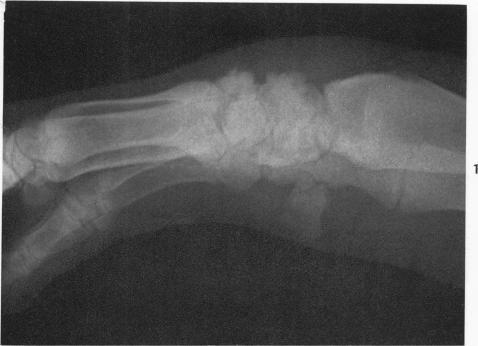

The pathology of chronic arthritis following natural and experimental erysipelothrix infection of swine.

Am J Pathol. 1956 Nov-Dec;32(6):1241-51.